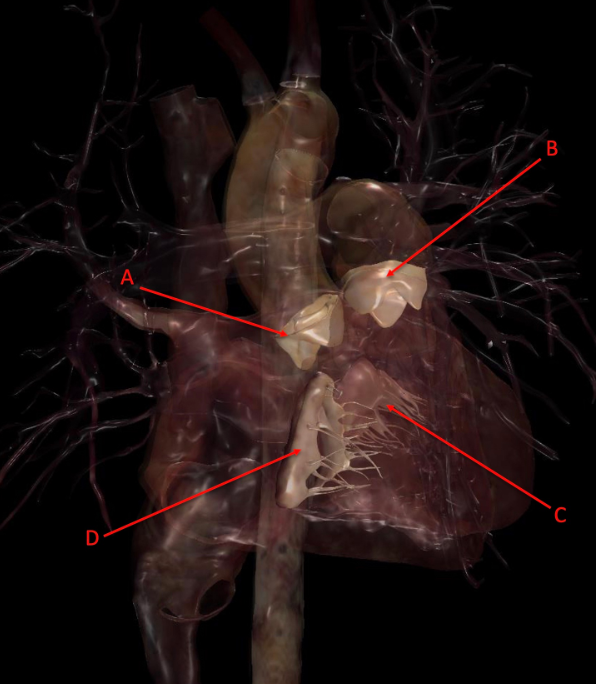

Q

Identify the following structure(s)

A

A. aortic semilunar valve

B. pulmonary semilunar valve

C. mitral valve

D. tricuspid valve